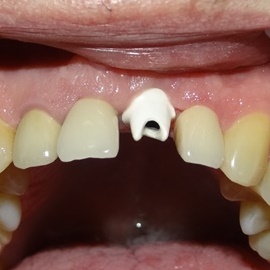

Po utracie zęba w przednim odcinku łuku zębowego należy zwrócić wzmożoną uwagę na aspekt estetyczny. Naczelnym przesłaniem odbudowy brakujących tkanek (anatomiczno-funkcjonalny kompleks tkanek: kość wyrostka zębodołowego + dziąsło + zęby) jest uzyskanie takiego wyniku, który jest najbliżej ideału, czyli takiej sytuacji jak gdyby nic się nie stało i w ogóle nie doszło do utraty zęba i tkanek około zębowych. Kluczem do sukcesu jest odtworzenie poprawnych stosunków anatomicznych: kość - dziąsło - ząb.

Korona protetyczna na implancie, funkcjonująca od roku 2003. Zdarzył się wypadek motocyklowy. Widzimy klucz do osiągnięcia sukcesu: mikrochirurgia i poprawna anatomiczna odbudowa tkanek. Tego nie zastąpi nawet najdroższy implant!

Pokazano etapową odbudowę brakujących tkanek, wraz z odbudową objętości i kształtu dziąsła.

Odbudowa tkanek i zębów przy wysokiej linii uśmiechu. Zadowalający wynik estetyczny.

Odbudowa brakującej kości, odbudowa anatomicznych stosunków dziąsła i korona całoceramiczna osadzona na łączniku cyrkonowym.